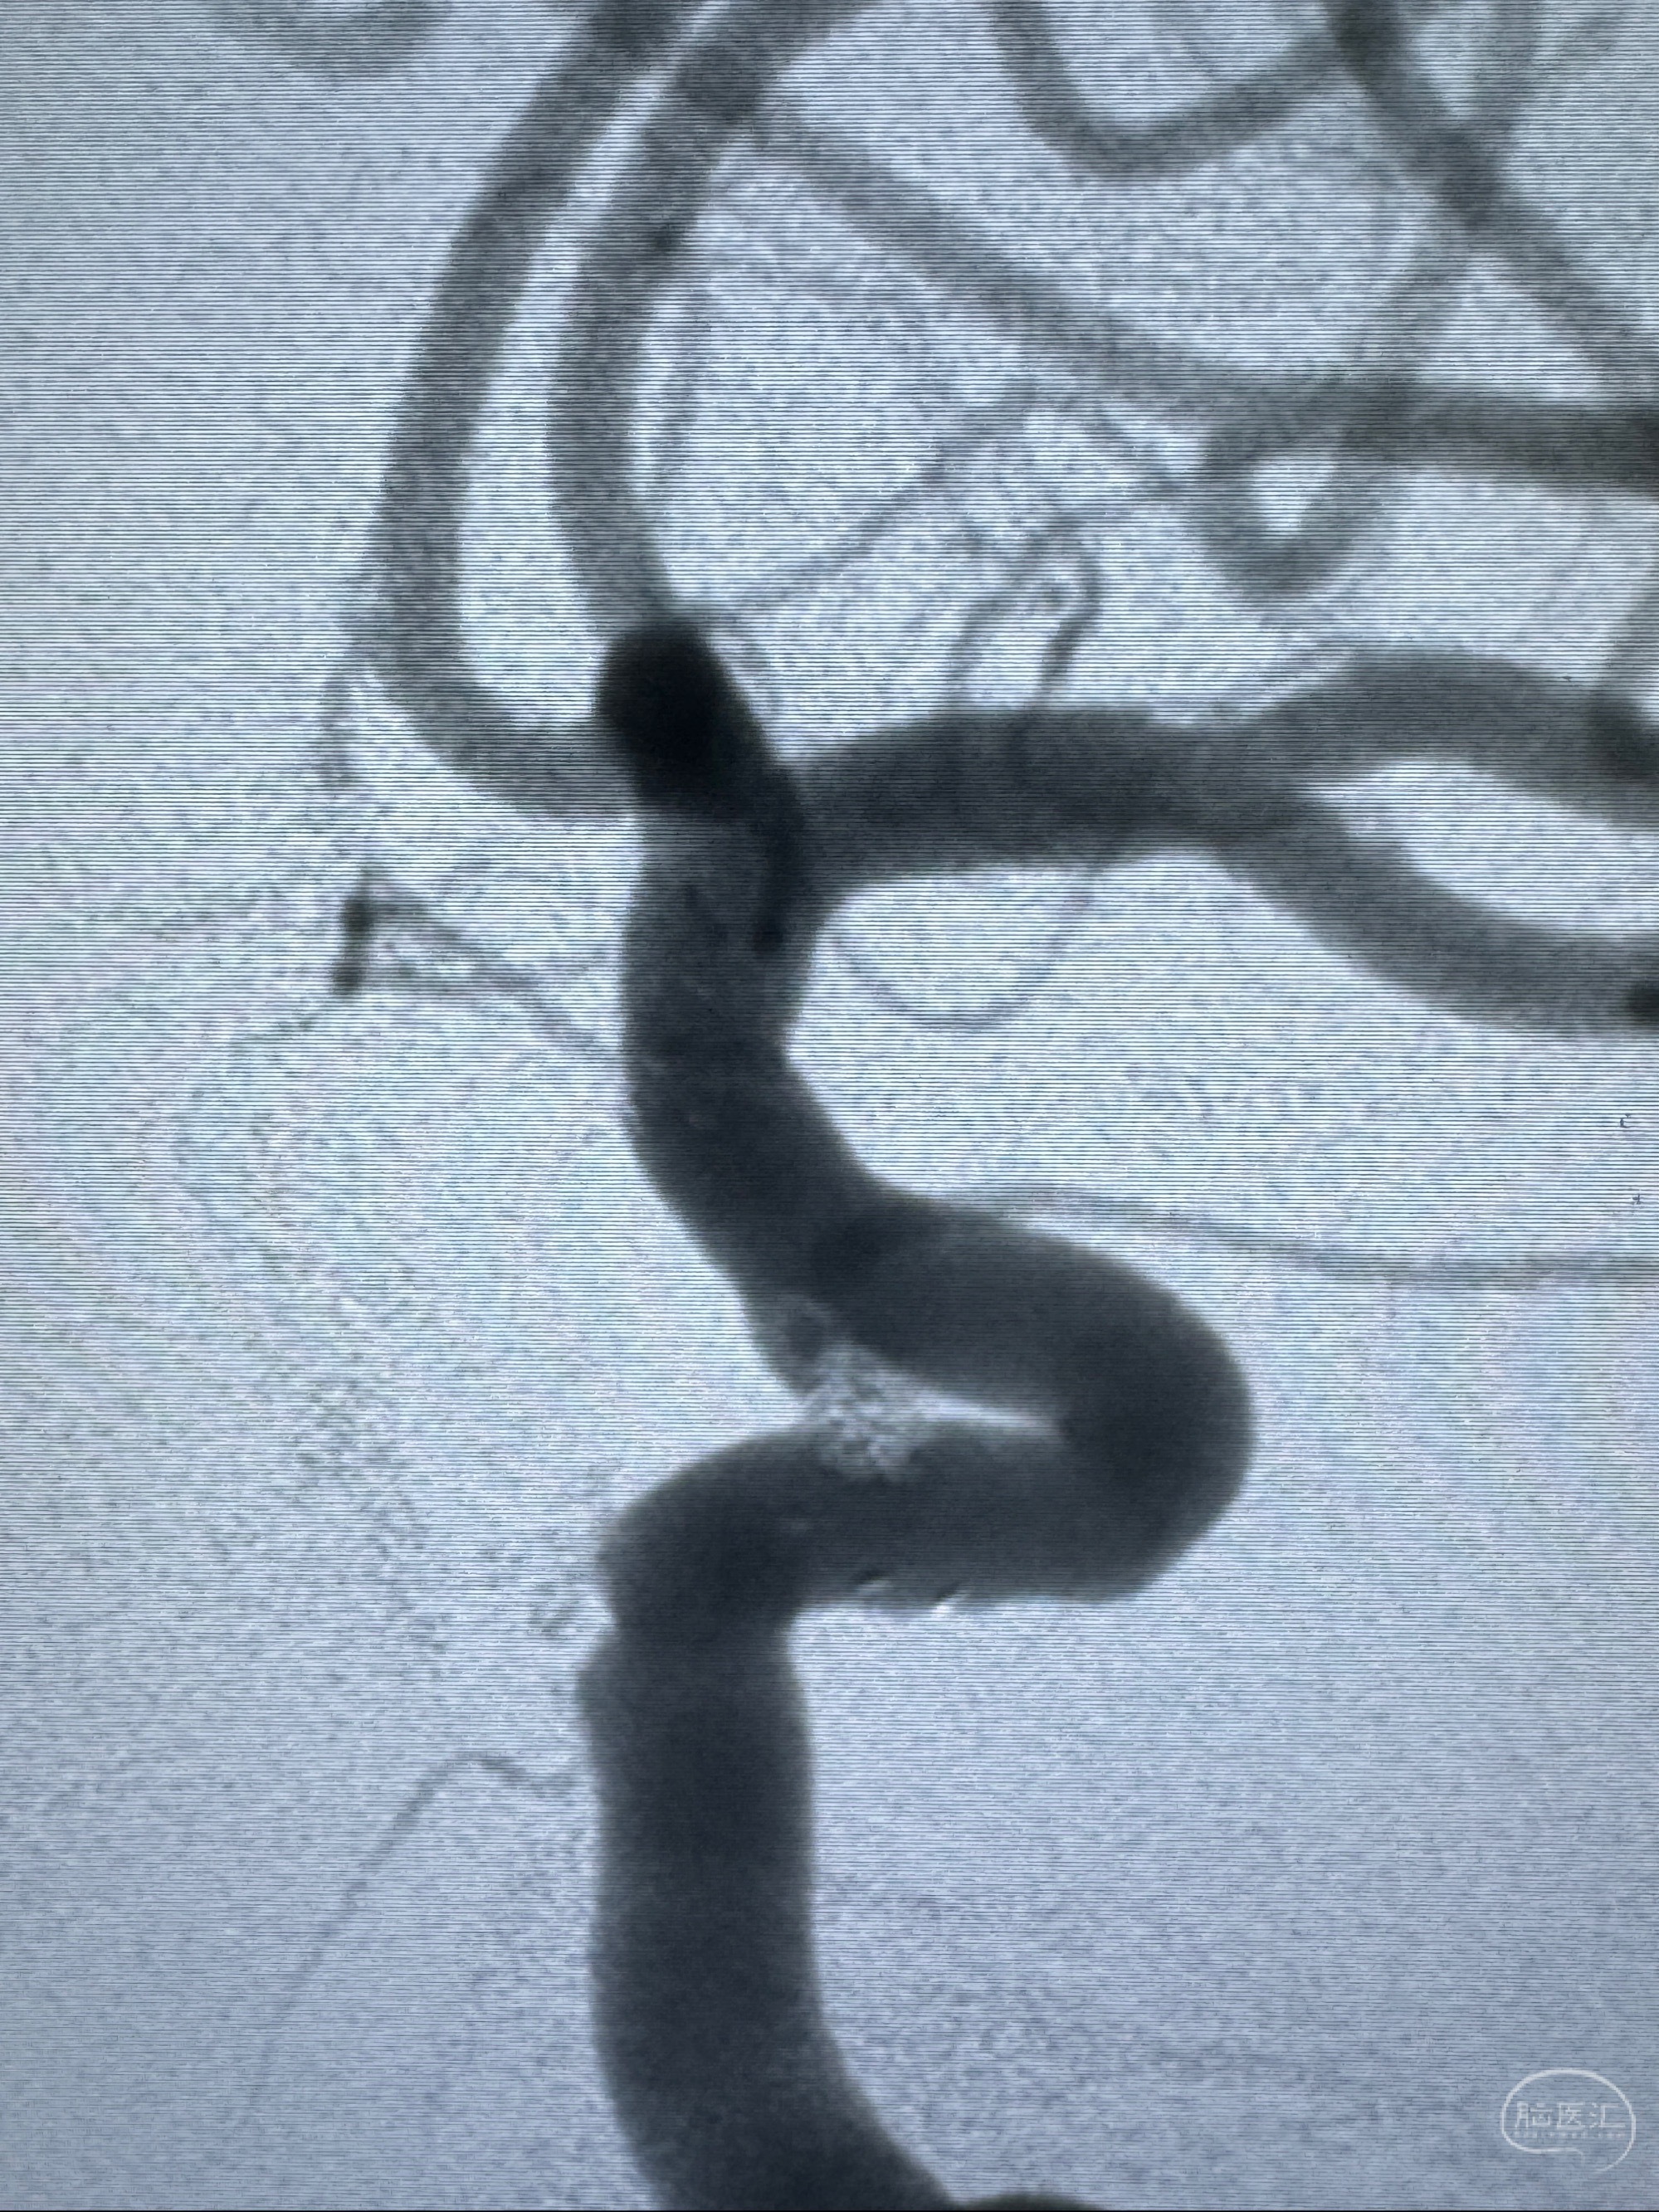

2023-11-03 蓝十字脑科医院 头颅CTA:左侧颈内动脉C6段微小动脉瘤可能(约2mm),右侧大脑前动脉A1段纤细(对侧优势),左侧大脑中动脉提前分叉。

2023-11-13DSA:左侧颈内动脉眼动脉后壁动脉瘤